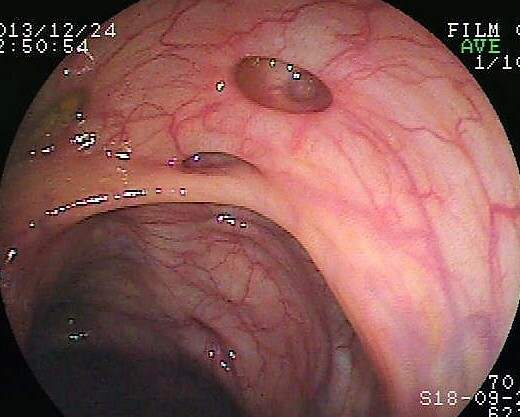

Iliitis-Endoskopie.jpg von Joachim Guntau.J. Guntau at de.wikipedia, CC BY-SA 2.0 DE, via Wikimedia Commons

InfoMorbus Crohn

Es handelt sich um eine chronisch-entzündliche Darmerkrankung, die alle Abschnitte des Gastrointestinaltrakts befällt und schubweise verläuft. Die Ursache ist multifaktoriell. Eine gefürchtete Komplikation ist insbesondere die Fistelbildung.